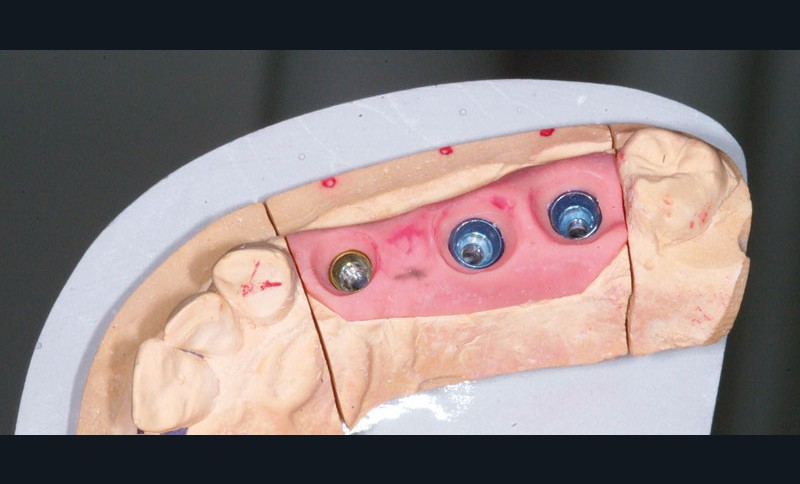

Le modèle de travail est fabriqué au laboratoire, des piliers CFAO Atlantis™ sont réalisés en fonction du bridge antagoniste transitoire.

Le modèle de travail est fabriqué au laboratoire, des piliers CFAO Atlantis™ sont réalisés en fonction du bridge antagoniste transitoire.